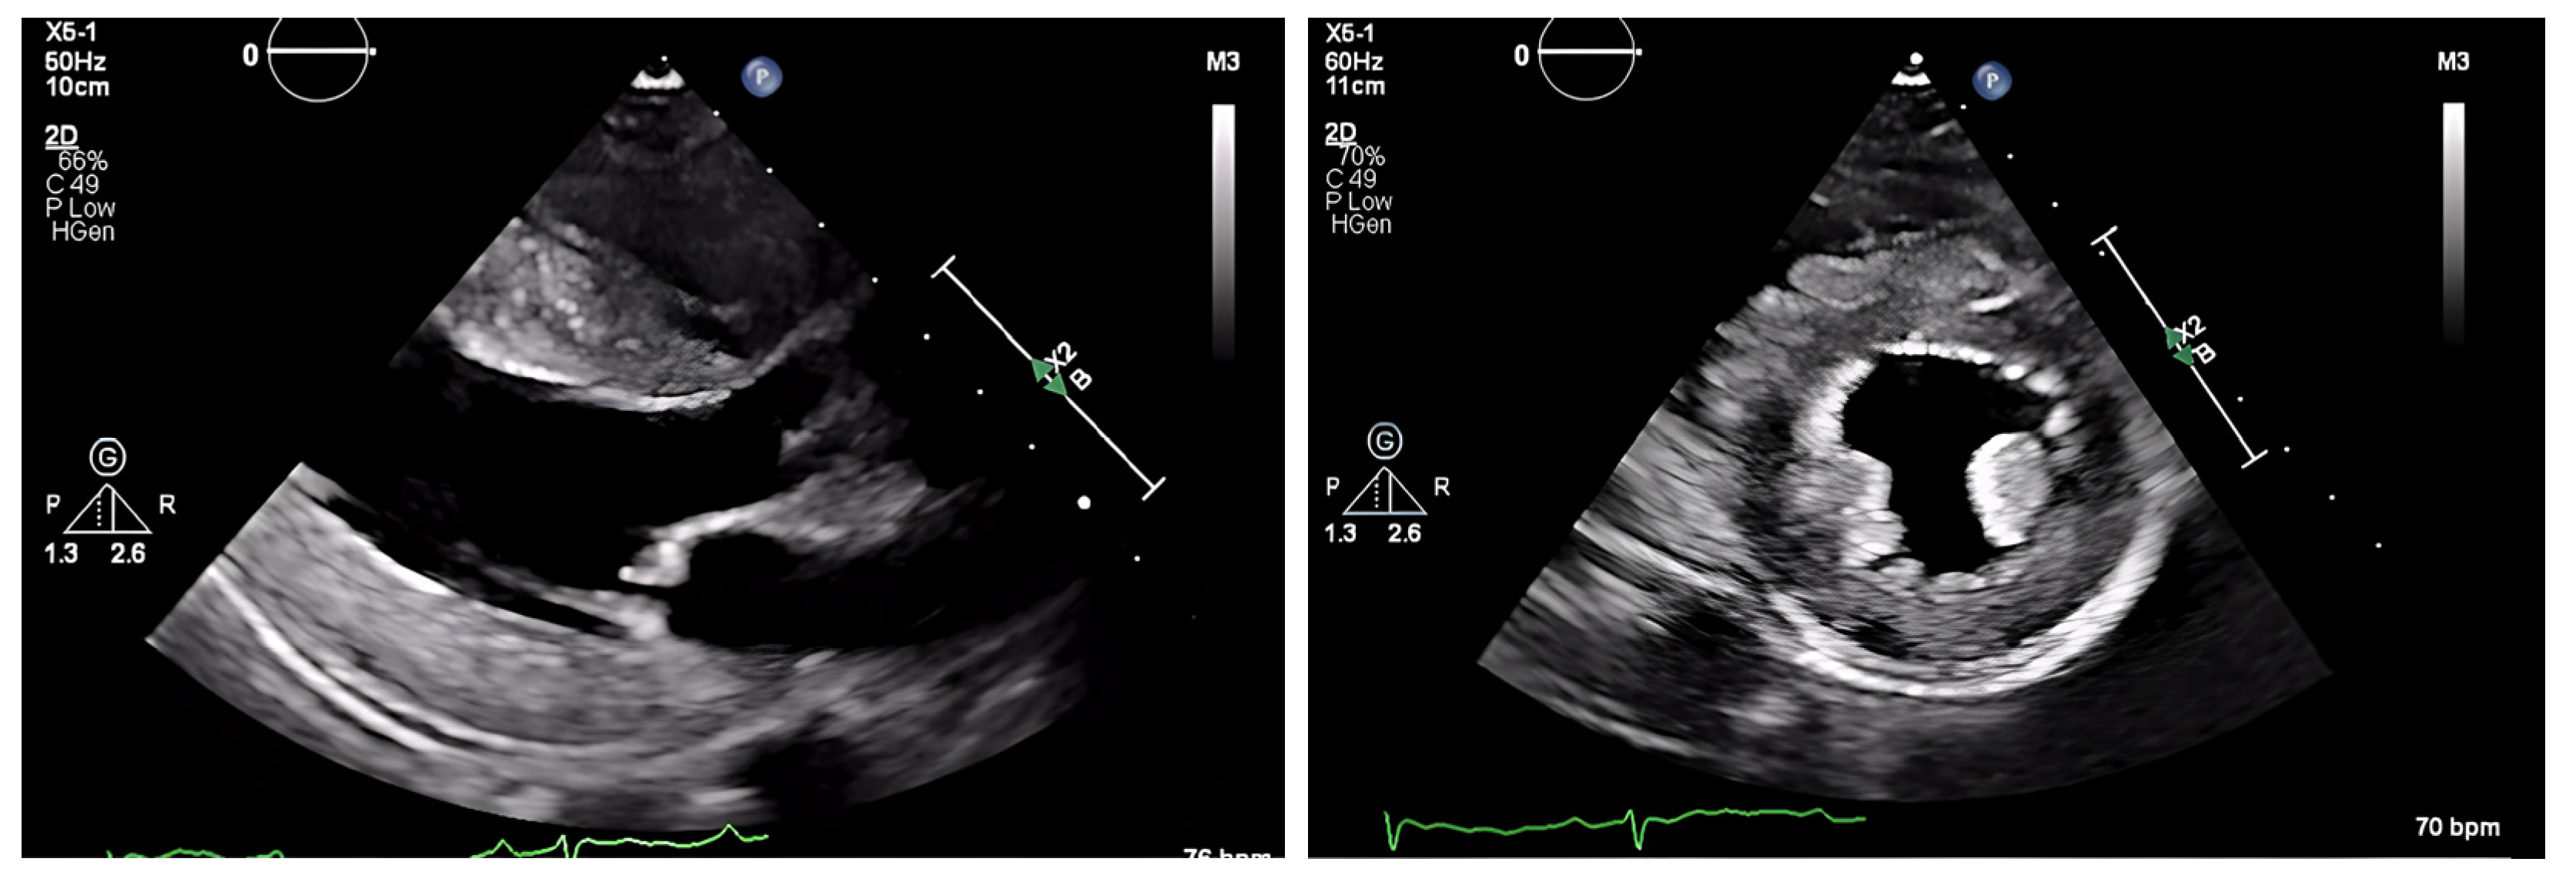

The chest radiograph did not show any acute findings. Electrocardiogram (ECG) (Figure 1) showed normal sinus rhythm with first-degree atrioventricular block, left axis deviation, and low voltage in limb leads. No prior echocardiogram (ECHO) was available, so an initial ECHO was obtained showing preserved ventricular ejection fraction (EF), moderate left ventricular hypertrophy (LVH), stage II diastolic dysfunction, and small pericardial effusion (Figure 2 and Figure 3).

On ECHO, the characteristic finding is symmetric biventricular wall thickening (LV > 12 mm, and often ≥15 mm) with non-dilated ventricles and diastolic dysfunction. Biatrial enlargement commonly occurs from elevated ventricular filling pressure and direct atrial amyloid deposition. There is a risk for atrial thrombus formation (in the absence of arrhythmias) as amyloid infiltration contributes to an irregular endocardial surface, decreased atrial contractility, and decreased stroke volume (SV) [33].

Valvular thickening may be present and can help differentiate CA from hypertensive heart disease [27]. EF is initially preserved with systolic dysfunction absent until advanced stages are reached when sequelae of myocyte necrosis and fibrosis start affecting systolic function. A hyperechoic “granular sparkling” appearing myocardium may be present. 2D speckle ECHO allows for analysis of the longitudinal axis. Impaired longitudinal strain in the basal and midventricular wall with sparing of the apical region is a characteristic finding. This finding has a high sensitivity rate (90–95%) and a high specificity rate (80–85%) [28]. It is also common to see small pericardial effusions, though this is nonspecific.

Figure 2. ECHO showing a discrepancy between the wall mass and electrical activity on ECG.